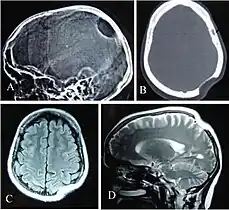

X-ray (A), CT scan (B) and MRI (C, D) show osteolysis of bone in the skull of an individual with Gorham-Stout disease.

Bone remodeling is regulated by mutual cross-regulation between osteoclasts and osteoblasts. As a result, the dysfunction of CSF1R signaling directly affects the reabsorption (osteoclasts) and indirectly affects bone deposition (osteoblasts). In inflammatory arthritis conditions such as rheumatoid arthritis, psoriatic arthritis, and Crohn's disease, proinflammatory cytokine TNF-α is secreted by synovial macrophages which stimulates stromal cells and osteoblasts to produce CSF-1. Increased CSF-1 promotes proliferation of osteoclasts and osteoclast precursors and increases osteoclast bone reabsorption. This pathogenic increase in osteoclast activity causes abnormal bone loss or osteolysis.[14] In animal models of rheumatoid arthritis, administration of CSF-1 increases the severity of disease whereas Csf1r loss-of-function reduces inflammation and joint erosion.[10] In a rare bone disease called Gorham‐Stout disease, elevated production of CSF-1 by lymphatic endothelial cells similarly produces excessive osteoclastogenesis and osteolysis.[8] Additionally, postmenopausal loss of estrogen has also been found to impact CSF1R signaling and cause osteoporosis. Estrogen deficiency causes osteoporosis by upregulating production of TNF-α by activated T cells. As in inflammatory arthritis, TNF-α stimulates stromal cells to produce CSF-1 which increases CSF1R signaling in osteoclasts.[15]